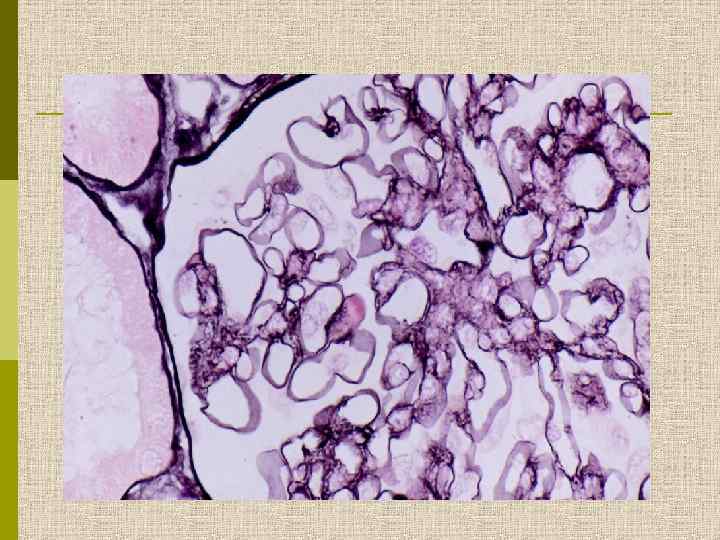

Мезангиопролиферативный гломерулонефрит (расширение мезангия + пролиферация мезангиоцитов)

Мезангиопролиферативный гломерулонефрит. Выраженная мезангиальная пролиферация и расширение мезангиального матрикса ( PAS)